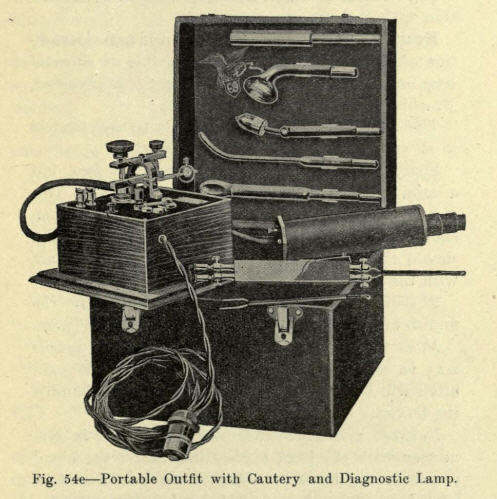

1869年4月29日

Beard引入电疗,治疗"神经衰弱"(neurasthenia),并沿用至今。